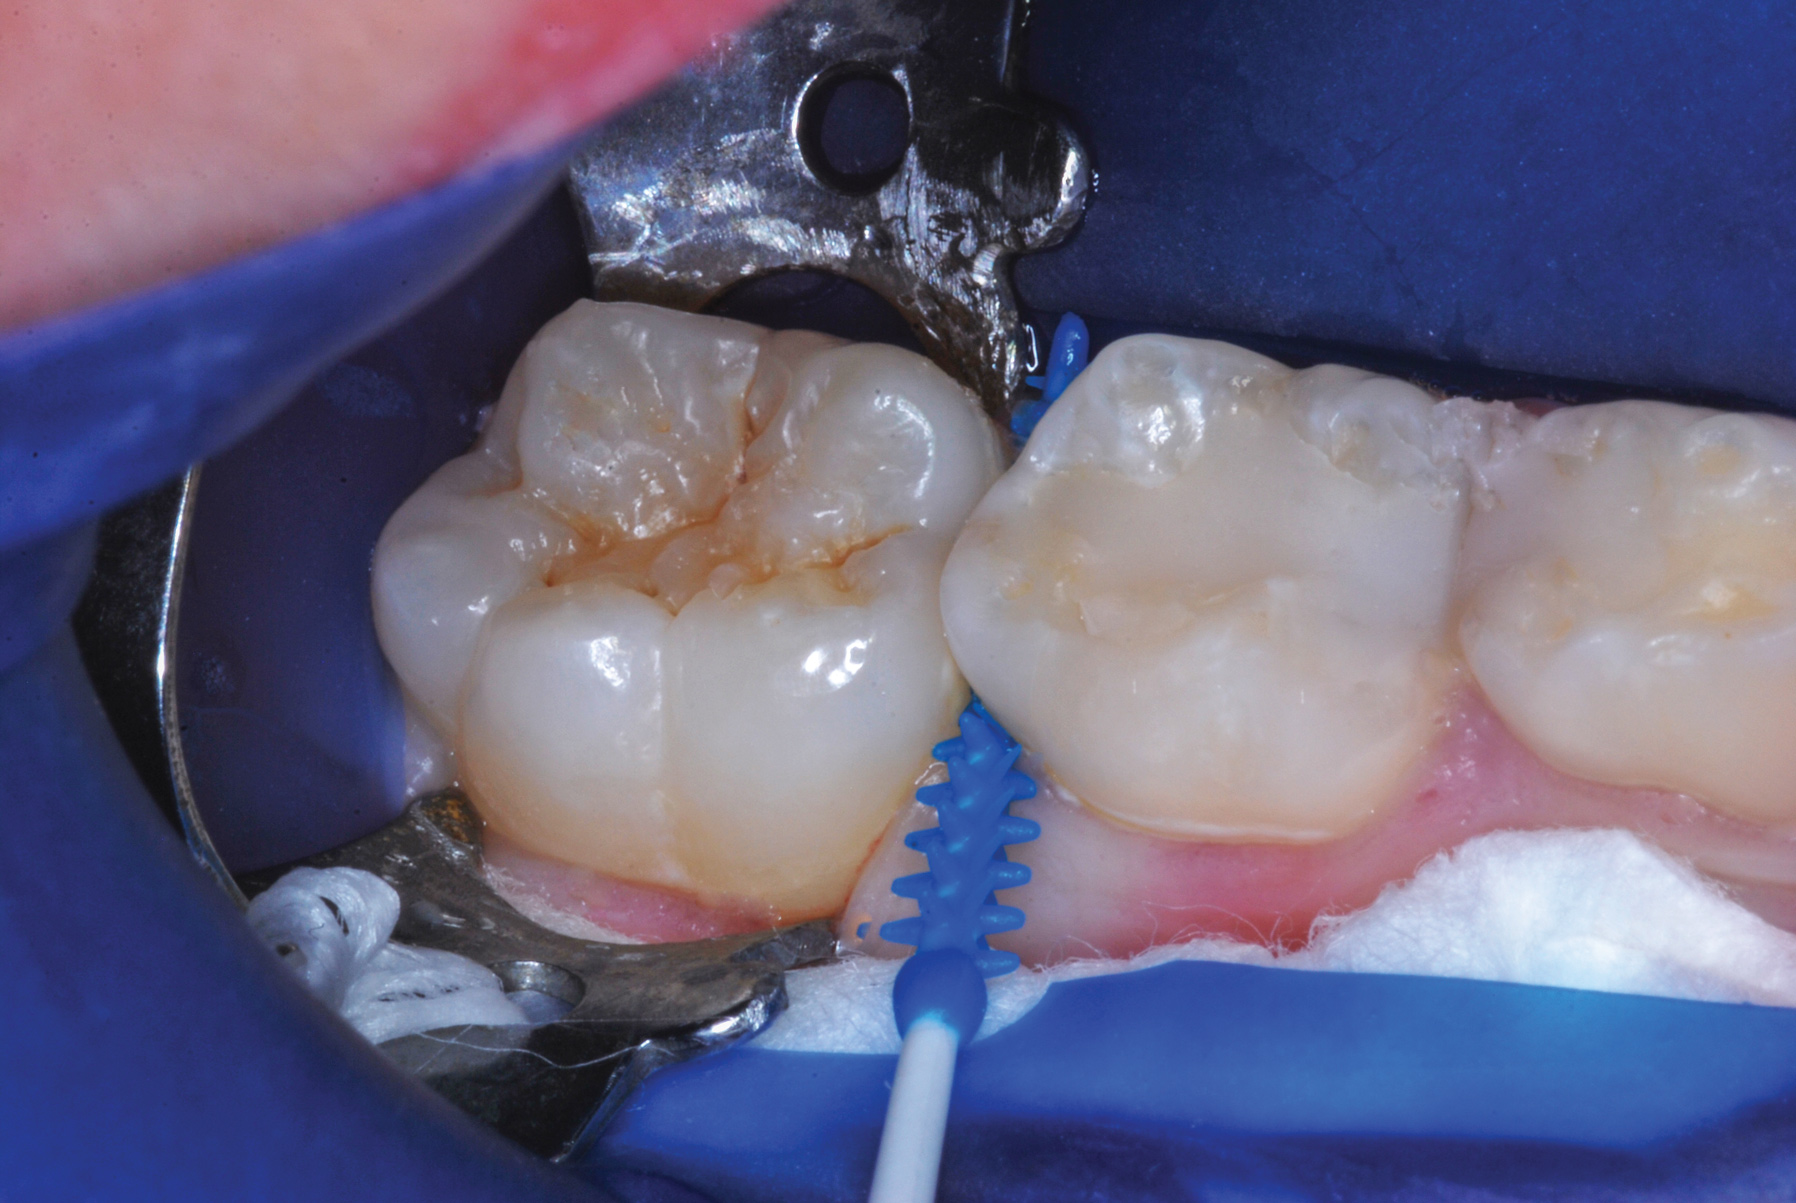

The authors' protocol for insertion of SDF-coated soft dental picks involves isolating the teeth with cotton rolls or other means, flossing the interproximal site to clear food debris and dental plaque, and then inserting a SDF-coated pick (Figure 1 and Figure 2) to saturate the contacting surfaces of the teeth with the fluid. This treatment is painless and requires no anesthetic. The pick should remain in place for at least 60 seconds and can be gently pulled in and out to agitate the fluid for enhanced surface coverage by capillary action. Additional SDF can be wiped on, using a small applicator, above the contact and in the buccal and lingual sluiceways. Excess fluid and any blood elicited may be blotted with a cotton swab. An additional 60-second insertion may be applied in the same way if there is radiographic evidence of a deeper decalcification or caries lesion. With the pick still in place, 5% (or 2.5%) fluoride varnish is painted over the treatment area, and the pick is then withdrawn.

Interproximal insertion of SDF is demonstrated in different patients in Figure 3 through Figure 11. Various diameters and brands of soft dental picks may be used depending on the closeness of the proximal surfaces and ease of insertion; for example, some picks are designed for use in wider spaces between teeth. This protocol also offers versatility. Figure 3, for example, shows the simultaneous use of three thin soft dental picks to saturate proximal surfaces with SDF in a teenaged patient; the treated regions were subsequently covered with fluoride varnish (Figure 4). This patient was initially treated in April 2019 (Figure 5), with an identical re-application 3 months later. As shown in Figure 6, the December 2019 bitewing film revealed good results with the possible exception of the contact regions of the maxillary first and second molars. New SDF application was completed in the December appointment.

Figure 7 illustrates the use of thicker picks in premolar interproximal sites. Additionally, multiple picks can be used in one quadrant or in one proximal site with good isolation to maximize fluid saturation (Figure 9), which the authors have found to be an excellent time-saving strategy. Preventive or interceptive applications of SDF may also be effectively used in interproximal sites in orthodontic patients (Figure 10).

Fig 8. Caries prevention with SDF is critical on distal surfaces of primary second molars to avoid caries infection on mesial surfaces of permanent first molars. Note the Class 2 restorations in both primary molars in this 9-year-old patient whose first molar needed occlusal resin-based composite restoration.